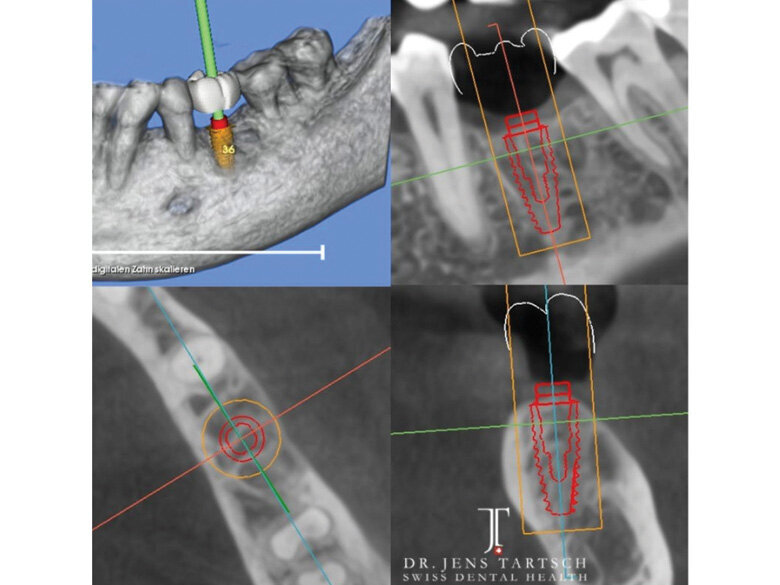

Fig. 1: Diagnostic 3-D treatment planning. Implant dimension and position with SMOP guided-surgery system. (Photo: Jens Tartsch, DMD)

This case shows a ZERAMEX XT 4.2 x 10 mm implant placed in a healed extraction and grafted site. The implant placement was done four months post-tooth extraction and grafting.

ZERAMEX XT is a two-piece, screw-retained system that functions surgically and restoratively like current titanium implants.